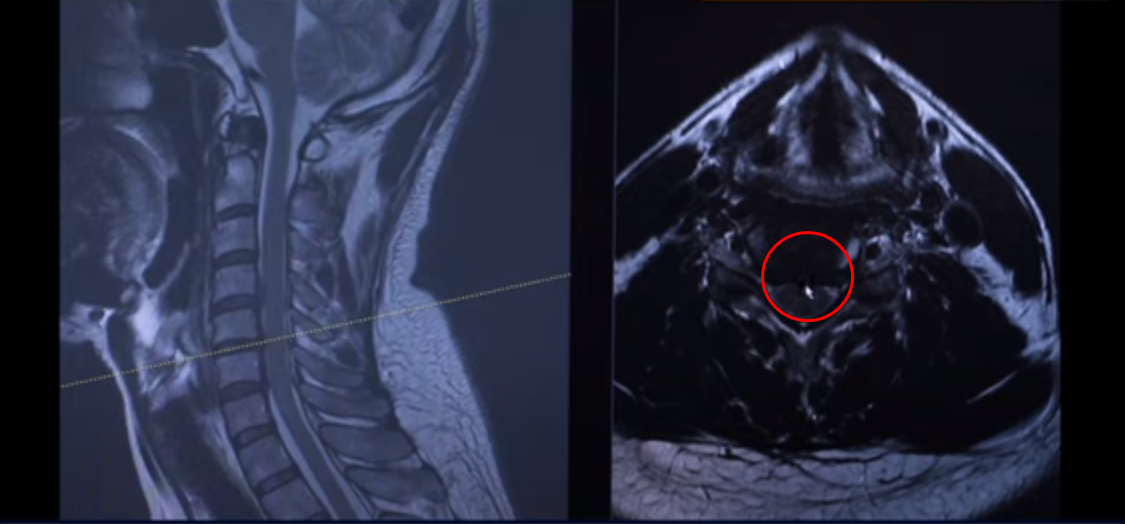

마지막 이 마디를 보시면 디스크가 조금 밀려서 올라가 있습니다. 이게 왼쪽으로 밀려 나와 있습니다.

이 환자분 증상이 목에 담결림 증상 외에도 왼쪽 어깨 쪽 증상과 왼쪽 손의 저림 증상입니다. 그래서 이것 때문에 왼쪽에 증상이 있다 이렇게 보시면 됩니다.